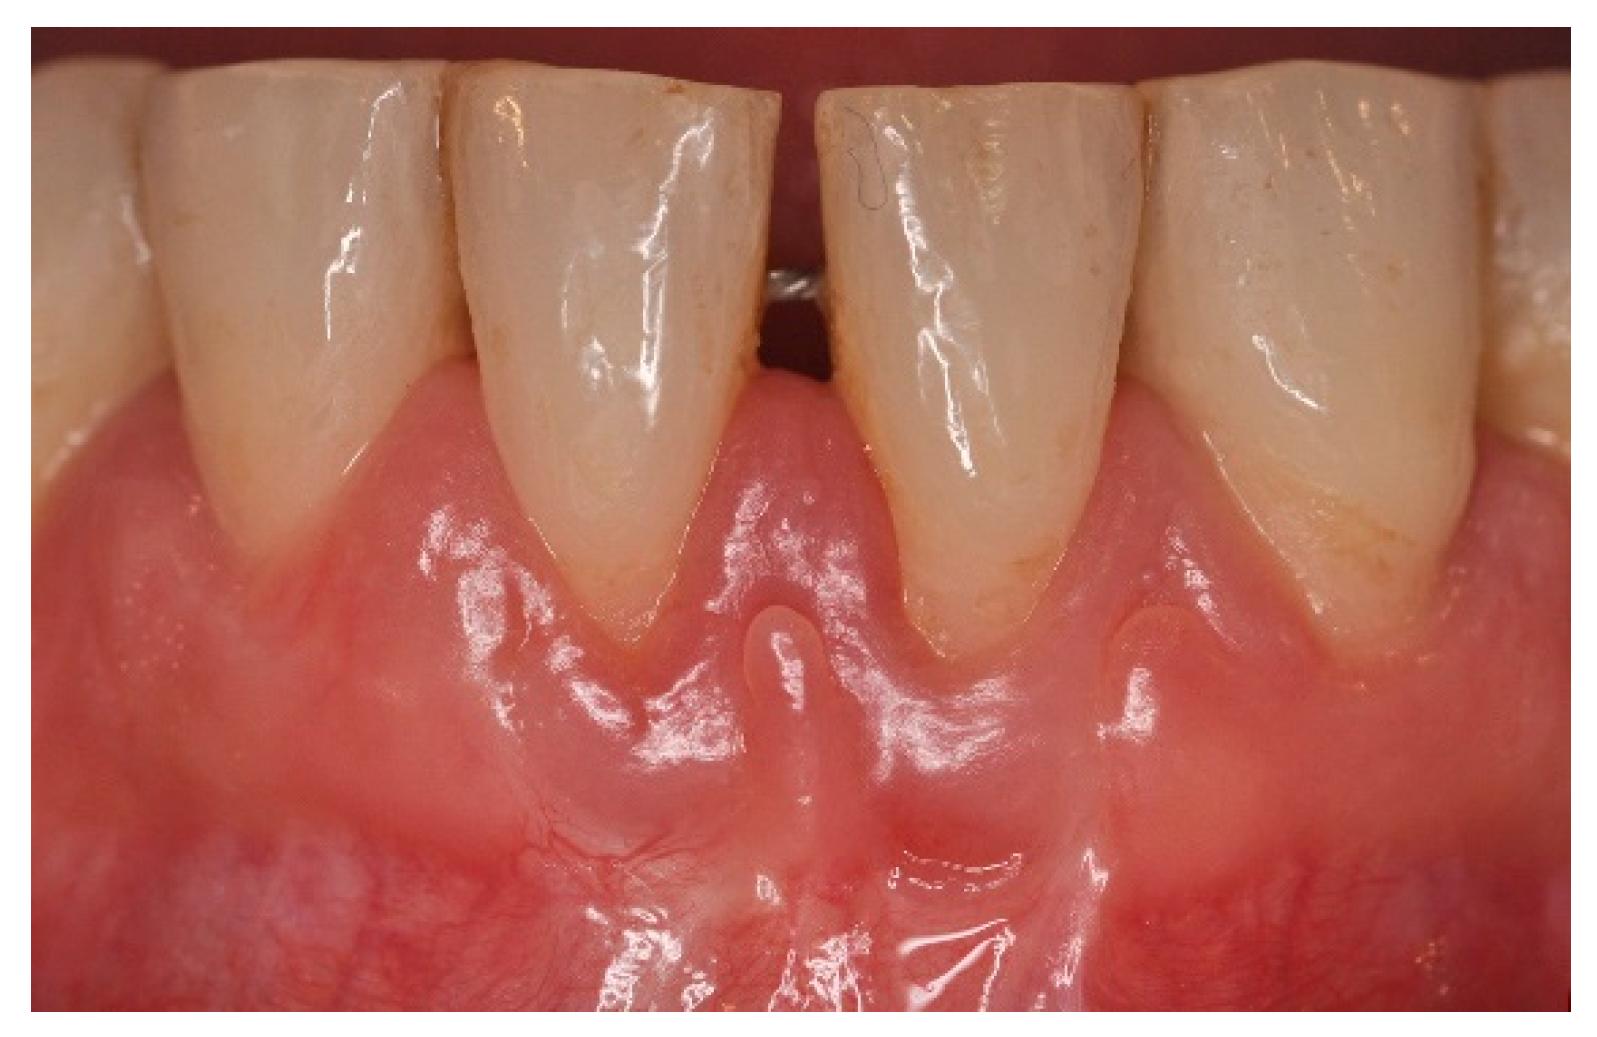

5. Materials and Methods

6. Results